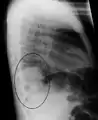

Right upper lobe pneumonia as marked by the circle.

The discovery of x-rays made it possible to determine the anatomic type of pneumonia without direct examination of the lungs at autopsy and led to the development of a radiological classification. Early investigators distinguished between typical lobar pneumonia and atypical (e.g. Chlamydophila) or viral pneumonia using the location, distribution, and appearance of the opacities they saw on chest x-rays. Certain x-ray findings can be used to help predict the course of illness, although it is not possible to clearly determine the microbiologic cause of a pneumonia with x-rays alone.